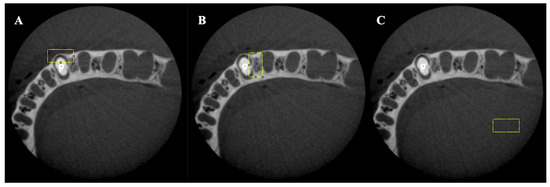

- Fontenele, R.C.; Farias Gomes, A.; Rosado, L.P.L.; Neves, F.S.; Freitas, D.Q. Mapping the expression of beam hardening artefacts produced by metal posts positioned in different regions of the dental arch. Clin. Oral Investig. 2020, 25, 571–579. [Google Scholar] [CrossRef]